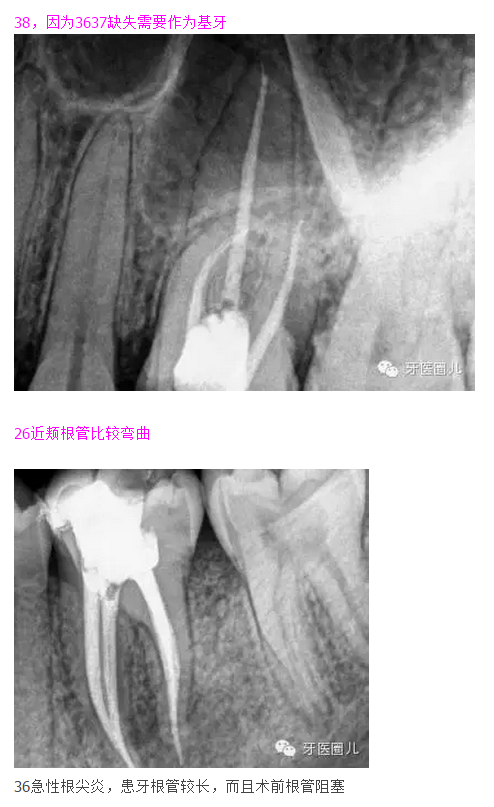

38,因?yàn)?637缺失需要作為基牙

這三個(gè)病例采用protaper器械,最后一個(gè)病例有不足,遠(yuǎn)中舌根根尖2mm有一個(gè)嚴(yán)重的向上彎曲,預(yù)備和充填時(shí)沒有到達(dá),術(shù)前評(píng)估和術(shù)中評(píng)估時(shí)覺得這個(gè)病例難度超過(guò)了我的操作范圍,但是患者沒有精力選擇更好的醫(yī)院,我于是和他講明狀況盡量做到我能做的了